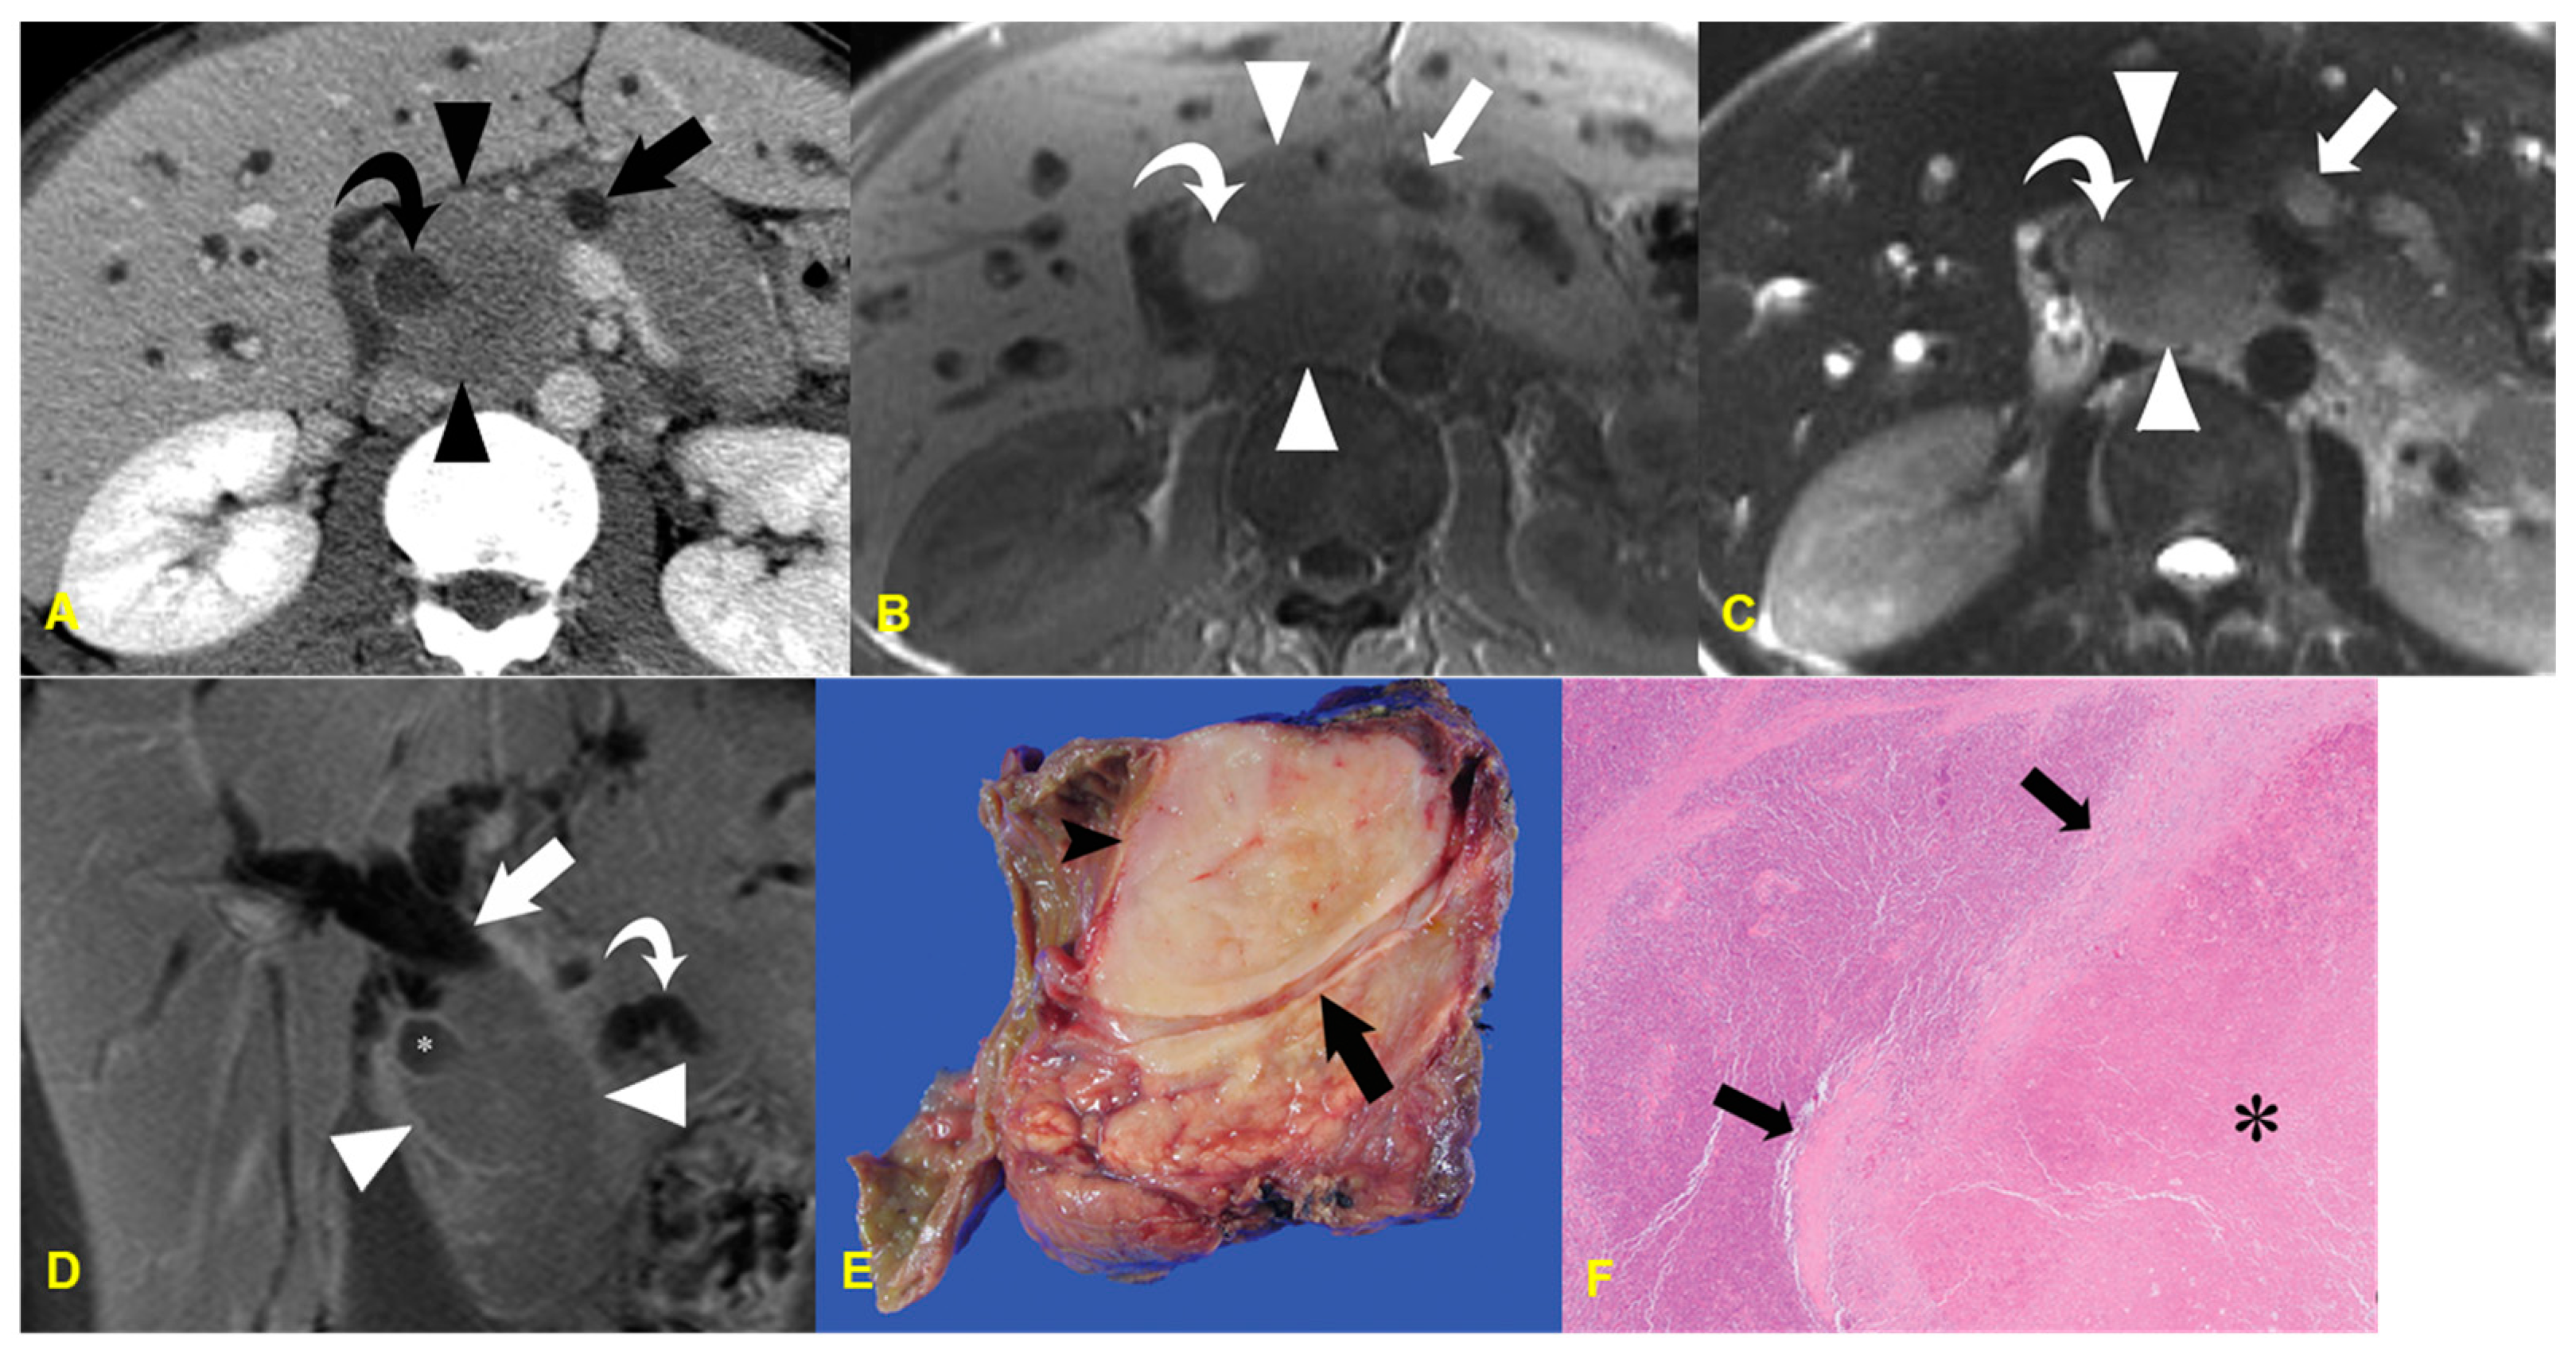

2. Colloid Carcinoma

2.1. Imaging Finding

2.2. Differential Diagnosis

| Colloid carcinoma | Very high SI and salt-and-pepper appearance on T2WI/ Internal sponge-like or mesh-like enhancement/No communication with pancreatic duct |